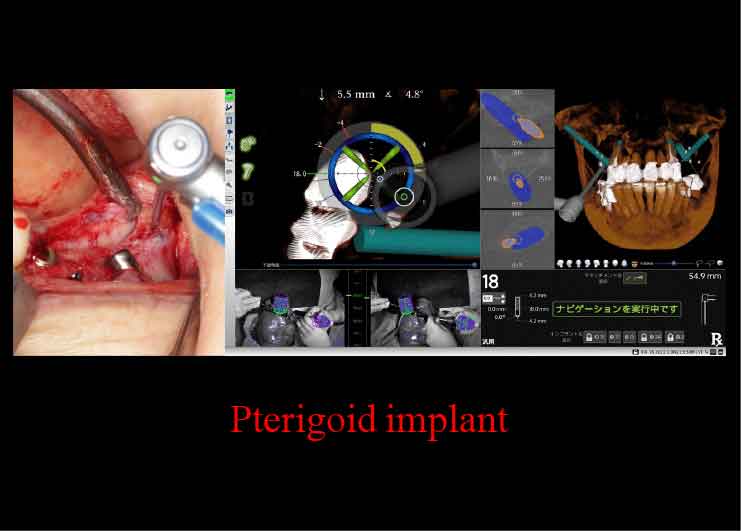

プテリゴイド(蝶形骨)インプラント

骨移植など、サイナスリフトを避けた手術を行えます。X-ガイドにより、正確な手術が可能です。